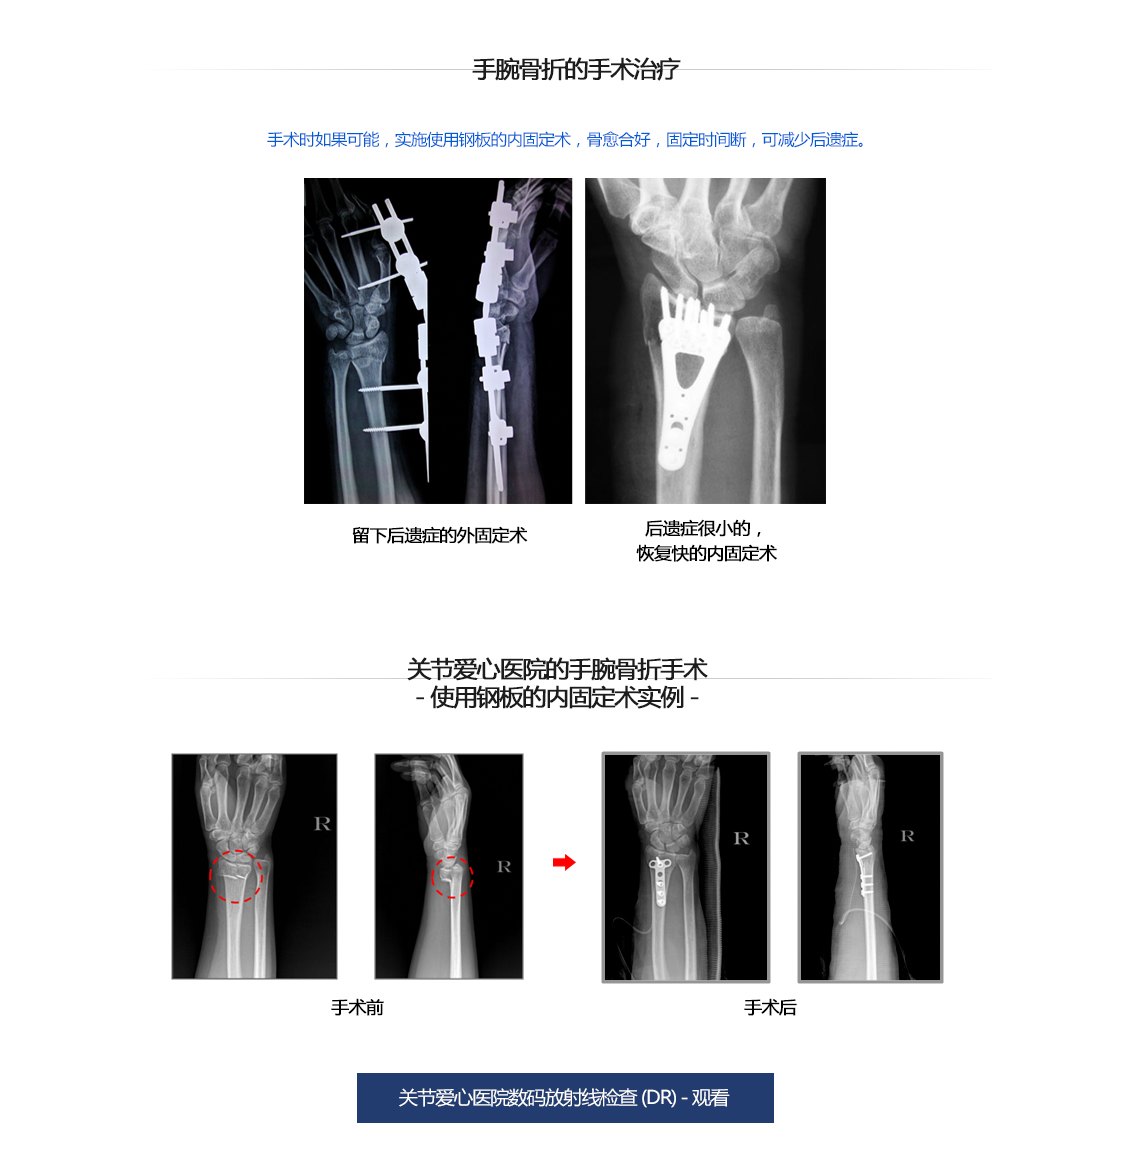

手腕关节骨折

手腕骨折手术